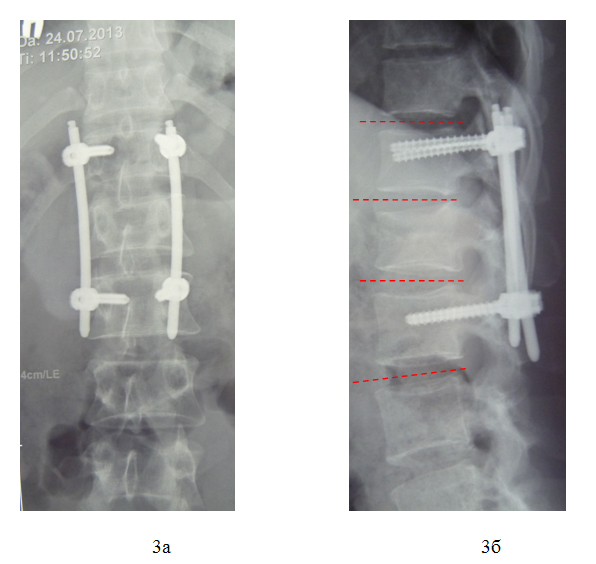

После предоперационной подготовки в кратчайшие сроки пациенту выполнена операция: Задняя внутренняя коррекция и фиксация позвоночника чрескожной транспедикулярной системой «Viper 2 3D» DePuy-Synthes.

На наш взгляд достигнуты поставленные цели:

- стабильная фиксация повреждённого позвоночно-двигательного сегмента,

- удовлетворительная коррекция сопутствующей посттравматической деформации,

- минимальная операционная травма,

- кратчайшие сроки реабилитации пострадавшего,

- полная удовлетворённость пациента результатами проведённого лечения.